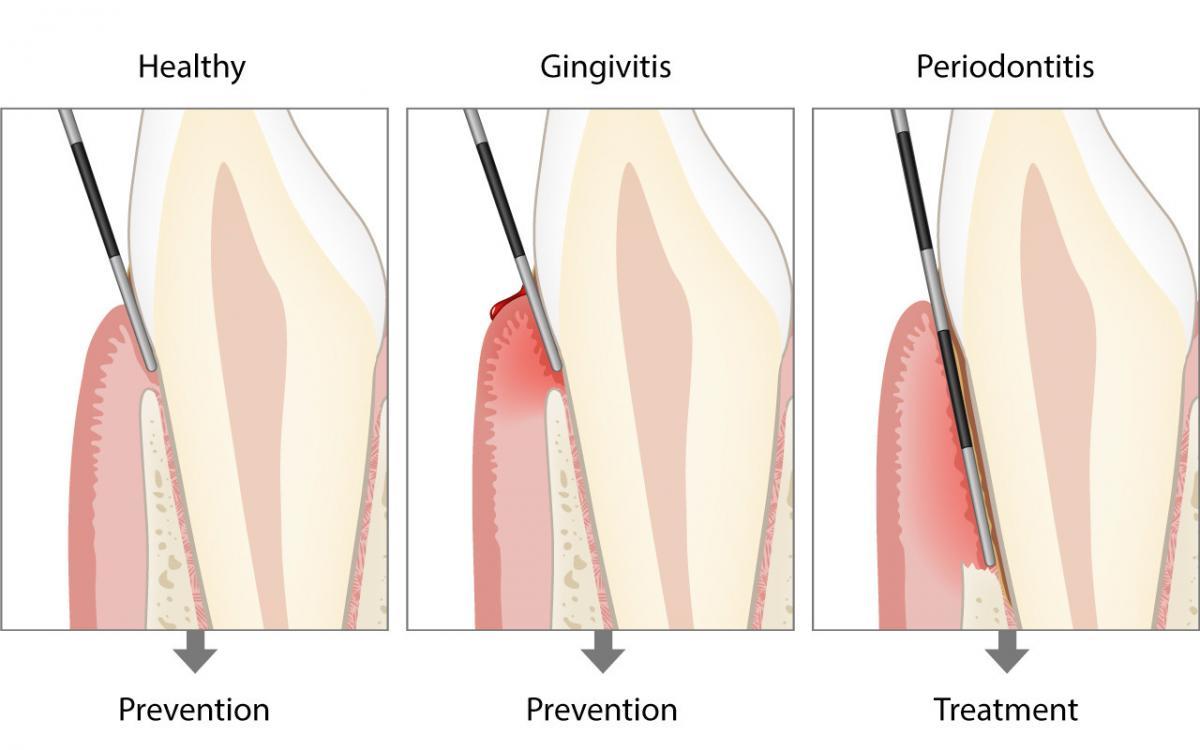

Erst die korrekte klinische Untersuchung in der Zahnarztpraxis mit einer sogenannten Zahnfleischsonde (Parodontalsonde) kann Aufschluss geben, ob das Zahnfleisch gesund ist, eine Zahnfleischentzündung (Gingivitis) oder bereits eine Erkrankung der Zahnverankerung (Parodontitis) vorliegt.

Bei einer ersten Kontrolle kann der Zahnarzt oder die Dentalhygienikerin eine sogenannte parodontale Kurzuntersuchung durchführen, die nur wenige Minuten dauern wird.

Mit einer Zahnfleischsonde (Parodontalsonde) wird an ausgewählten Stellen schonungsvoll und millimetergenau die Eindringtiefe am Zahnfleischrand gemessen.

Nach dieser Kurzuntersuchung werden weitere Abklärungen nur dann durchgeführt, wenn dabei Zeichen für den Abbau der Zahnverankerung gefunden wurden. Diese Abklärungen beinhalten den sogenannten Parodontalstatus sowie zusätzliche Röntgenbilder.

Die millimetergenaue klinische Sondierung mit der Zahnfleischsonde zur Ausmessung der Zahnfleischtaschen und der Höhe des Kieferknochens sind zur Diagnose der Parodontitis unverzichtbar.

Zusätzlich wird in einem sogenannten Parodontalstatus die Höhe des Kieferknochens (Attachmentniveau) millimetergenau festgehalten. Ein Parodontalstatus ist zur Diagnostik und Behandlungsplanung einer Parodontitis unverzichtbar. Der Parodontalstatus kann in jeder Zahnarztpraxis online aufgezeichnet und weiterverwendet werden: www.parodontalstatus.ch.